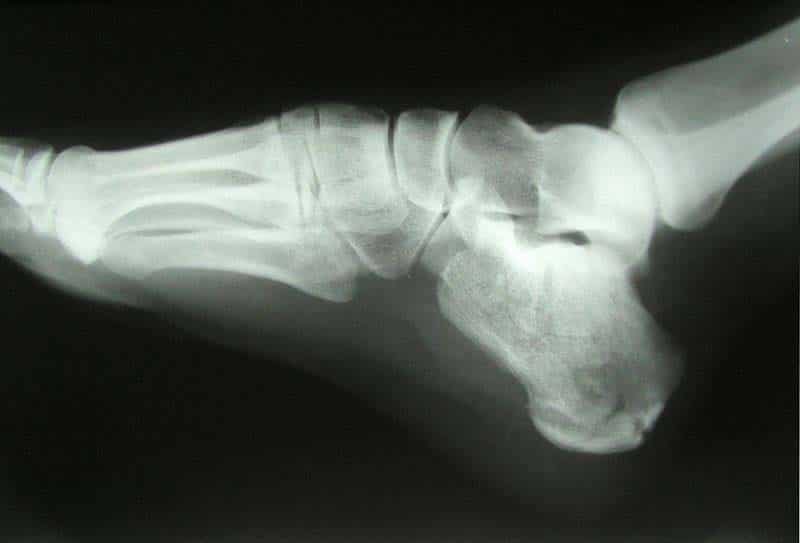

The subtalar joint is an articulation between two of the tarsal bones in the foot – the talus and calcaneus. The joint is classed structurally as a synovial joint, and functionally as a plane synovial joint. This article will look at the anatomy of the subtalar joint – its articulating surfaces, movements and neurovascular supply. Pro Feature - 3D Model You've Discovered a Pro Feature Access our 3D Model Library Explore, cut, dissect, annotate and manipulate our 3D models to visualise anatomy in a dynamic, interactive way. Learn More Articulating Surfaces The subtalar joint is formed between two of the tarsal bones: Inferior surface of the body of the talus – the posterior talar articular surface. Superior surface of the calcaneus – the posterior calcaneal articular facet. As is typical for a synovial joint, these surfaces are covered by articular cartilage. Note: Some texts will refer to the talocalcaneal part of the talocalcaneonavicular joint as being part of the subtalar joint. Although this forms part of the functional joint, the true anatomical subtalar joint consists only of the surfaces mentioned above. By TeachMeSeries Ltd (2025) Fig 1The subtalar joint and interosseous talocalcaneal ligament. Stability The subtalar joint is enclosed by a joint capsule, which is lined internally by synovial membrane and strengthened externally by a fibrous layer. The capsule is also supported by three ligaments: Posterior talocalcaneal ligament Medial talocalcaneal ligament Lateral talocalcaneal ligament An additional ligament – the interosseous talocalcaneal ligament – acts to bind the talus and calcaneus together. It lies within the sinus tarsi (a small cavity between the talus and calcaneus), and is particularly strong; providing the majority of the ligamentous stability to the joint. Movements The subtalar joint is formed on an oblique axis and is therefore the chief site within the foot for generation of eversion and inversion movements. This movement is produced by the muscles of the lateral compartment of the leg. and tibialis anterior muscle respectively. The nature of the articulating surface means that the subtalar joint has no role in plantar or dorsiflexion of the foot. Neurovascular Supply The subtalar joint receives supply from two arteries and two nerves. Arterial supply comes from the posterior tibial and fibular arteries. Innervation to the plantar aspect of the joint is supplied by the medial or lateral plantar nerve, whereas the dorsal aspect of the joint is supplied by the deep fibular nerve. Calcaneal Fracture The calcaneus is often fractured in a ‘crush‘ type injury. The most common mechanism of damage is falling onto the heel from a height – the talus is driven into the calcaneus. The bone can break into several pieces, known as a comminuted fracture. Upon x-ray imaging, the calcaneus will appear shorter and wider. A calcaneal fracture can cause chronic problems, even after treatment. The subtalar joint is usually disrupted, causing the joint to become arthritic. The patient will experience pain upon inversion and eversion – which can make walking on uneven ground particularly painful. By Jojo (Own work) [CC-BY-SA-3.0], via Wikimedia Commons Fig 2X-ray of a calcaneal fracture. Do you think you’re ready? Take the quiz below Pro Feature - Quiz The Subtalar Joint Question 1 of 3 Submitting... Skip Next Rate question: You scored 0% Skipped: 0/3 1800 More Questions Available Upgrade to TeachMeAnatomy Pro Challenge yourself with over 1800 multiple-choice questions to reinforce learning Learn More Rate This Article